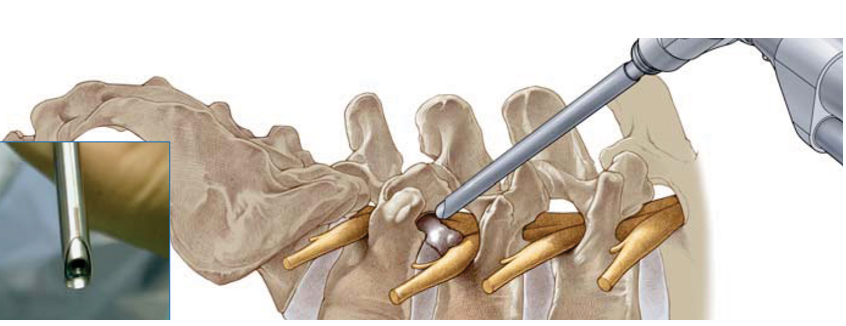

放置工作套管(工作通道)独特设计的套管顶端可以保护神经根免遭损伤

用C型臂确定工作套管放置的位置。正确的位置应该是放在神经根下方,椎间盘水平,顶端正好在中线,开口朝向突出的髓核。

放置椎间孔镜连接椎间孔镜到光源和摄像机。打开光源,调节白平衡,达到最佳彩色效果。把椎间孔镜放入工作套管。调节合适的水流量和压力对取得良好效果很重要。

椎间盘及神经根减压在整个手术过程中病人必须保持清醒和配合。有完整的椎间盘摘除器械,如神经探子、神经钩、神经提拉器、抓钳、咬钳、打孔器、切割器等,这些器械可以通过椎间孔镜的工作通道操作。

应用双击射频采用独特设计的可伸屈和转向的射频双极电极可以通过椎间孔镜的工作通道达到工作区域用于止血、消融髓核、以及通过组织收缩的作用封闭纤维环直径3 mm以下的裂口。